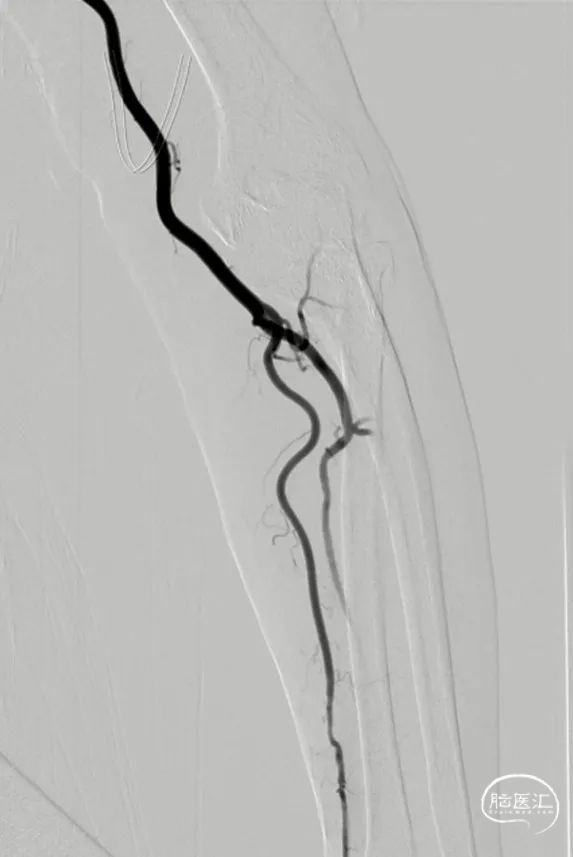

术前造影

术后造影